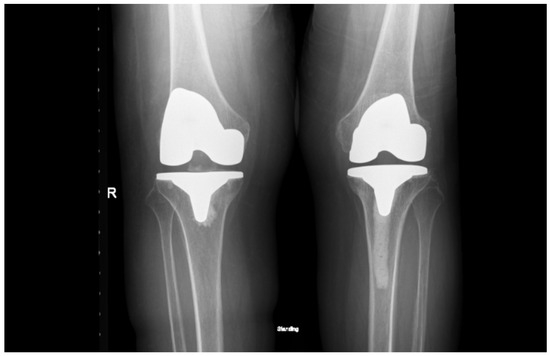

Figure 3.

Postoperative standing anteroposterior (left) and lateral (right) X-rays of the left knee showing the total knee prosthesis in situ. Notably, there is extensive cement penetration into the tibial canal, reflecting underlying bone brittleness associated with ochronotic arthropathy. No signs of aseptic loosening or periprosthetic fractures.